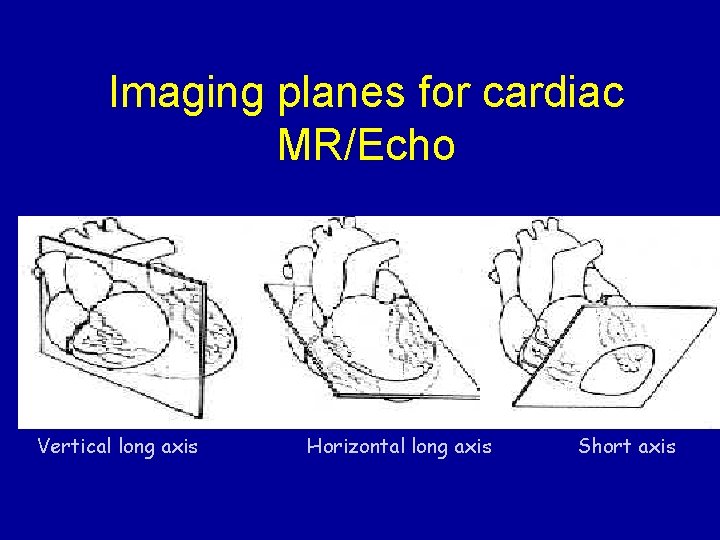

Imaging planes for cardiac MR/Echo Vertical long axis Horizontal long axis Short axis